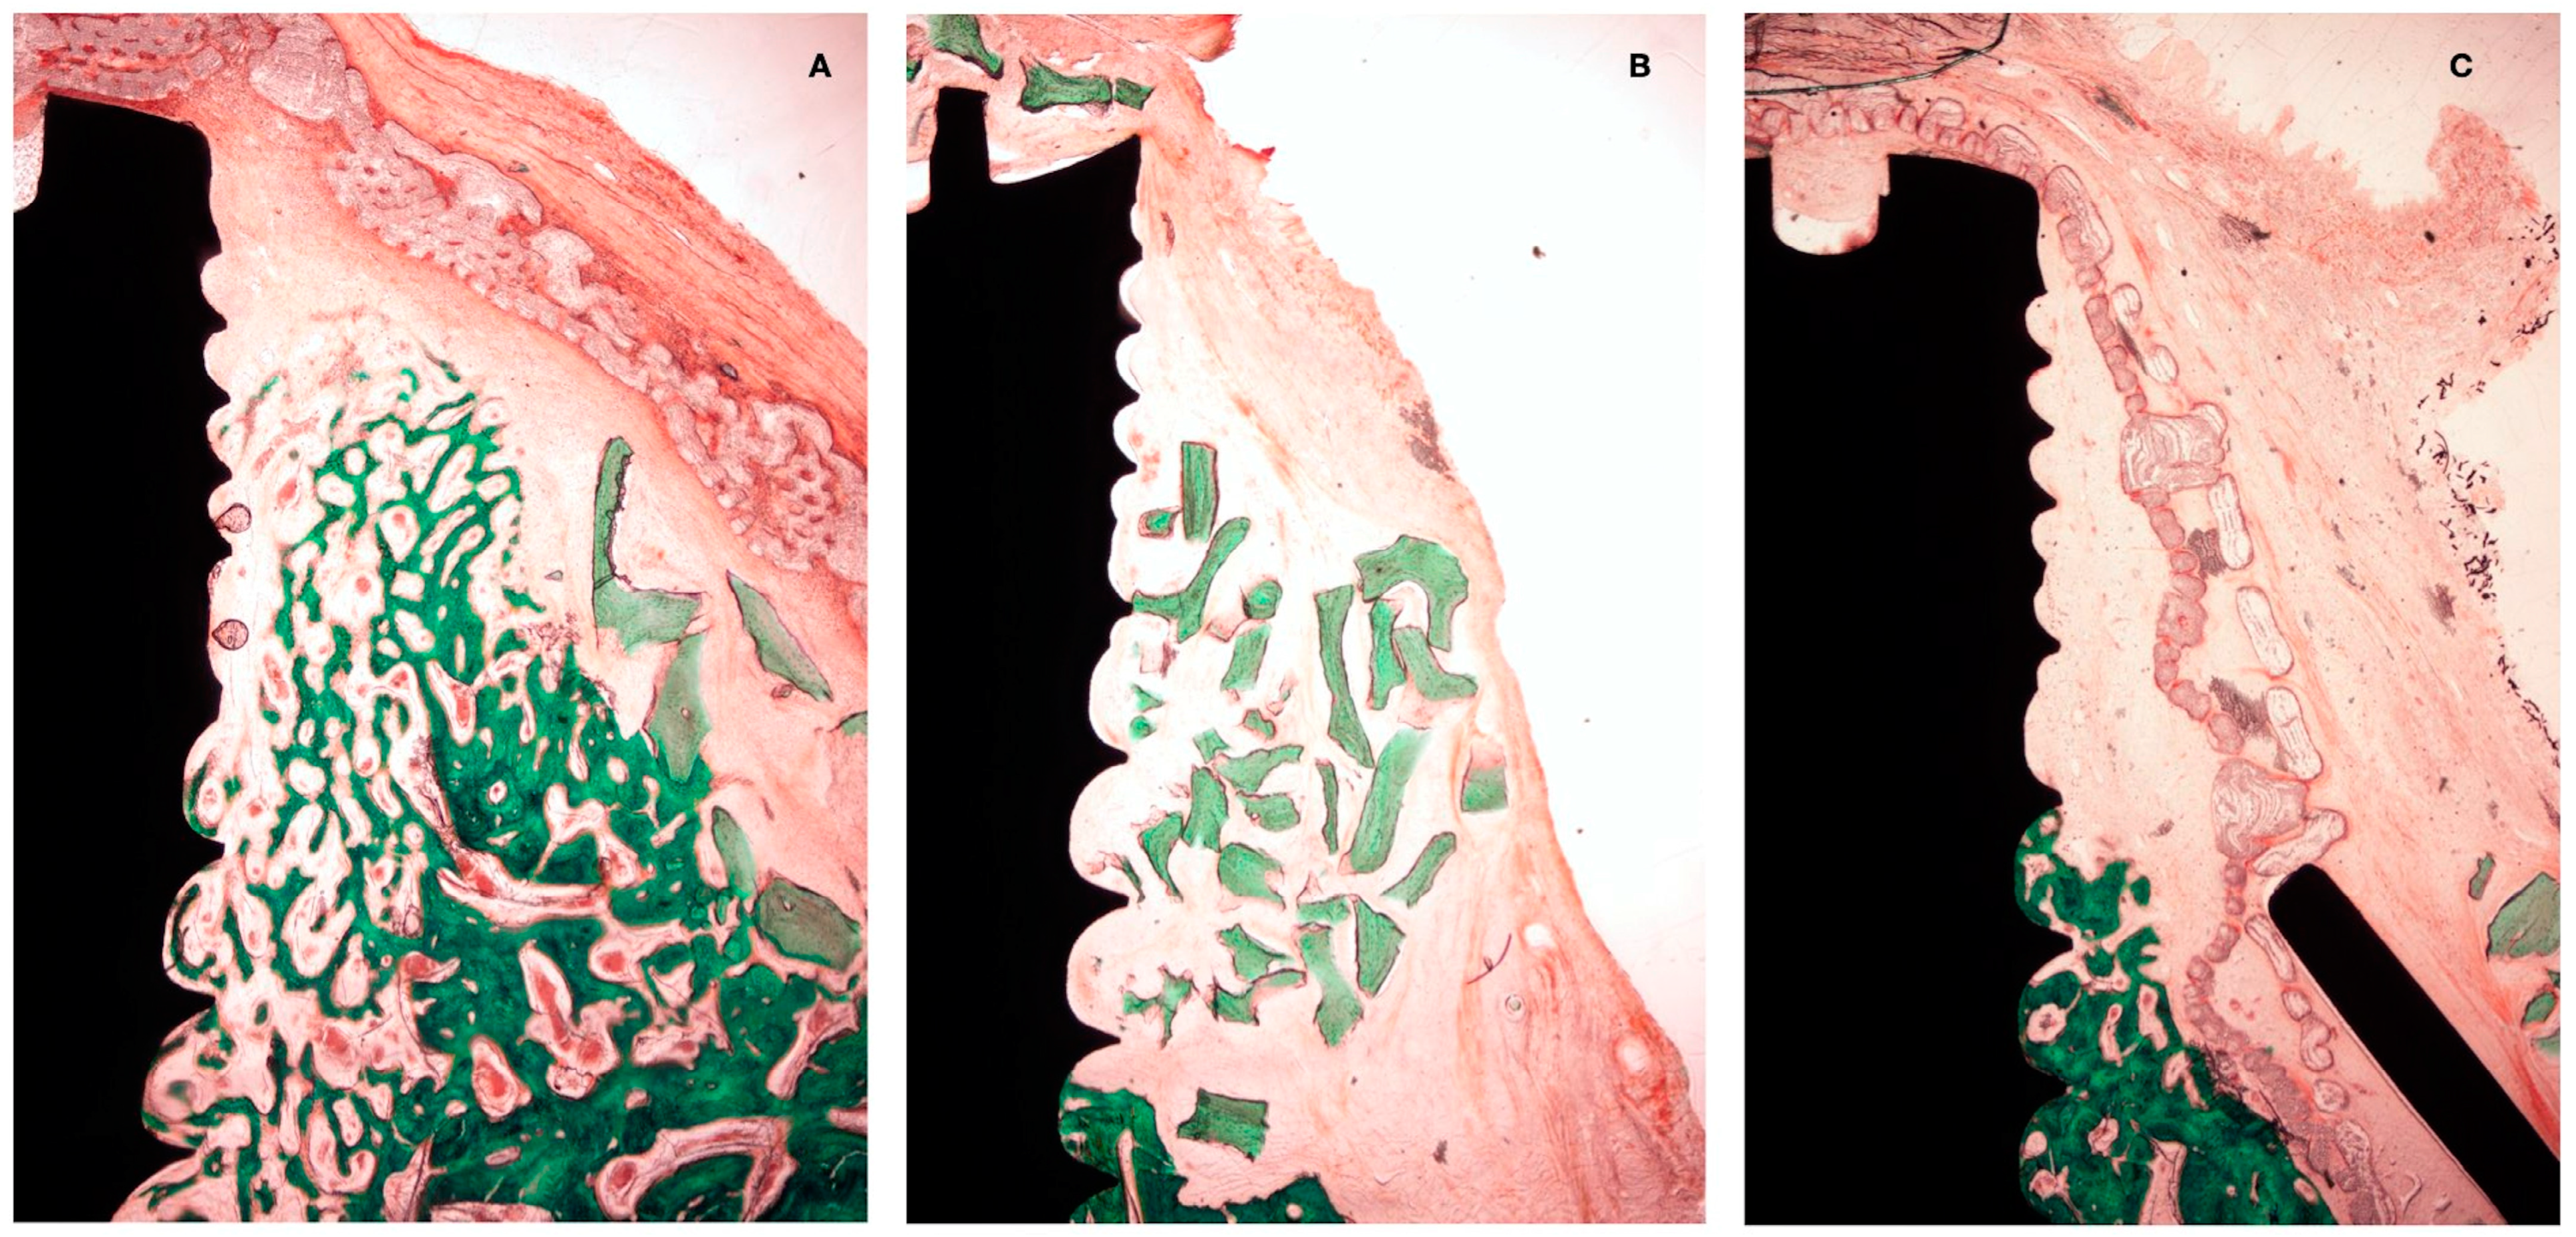

3.1. Histological Observations

3.2. Histo-Morphometric Measurements